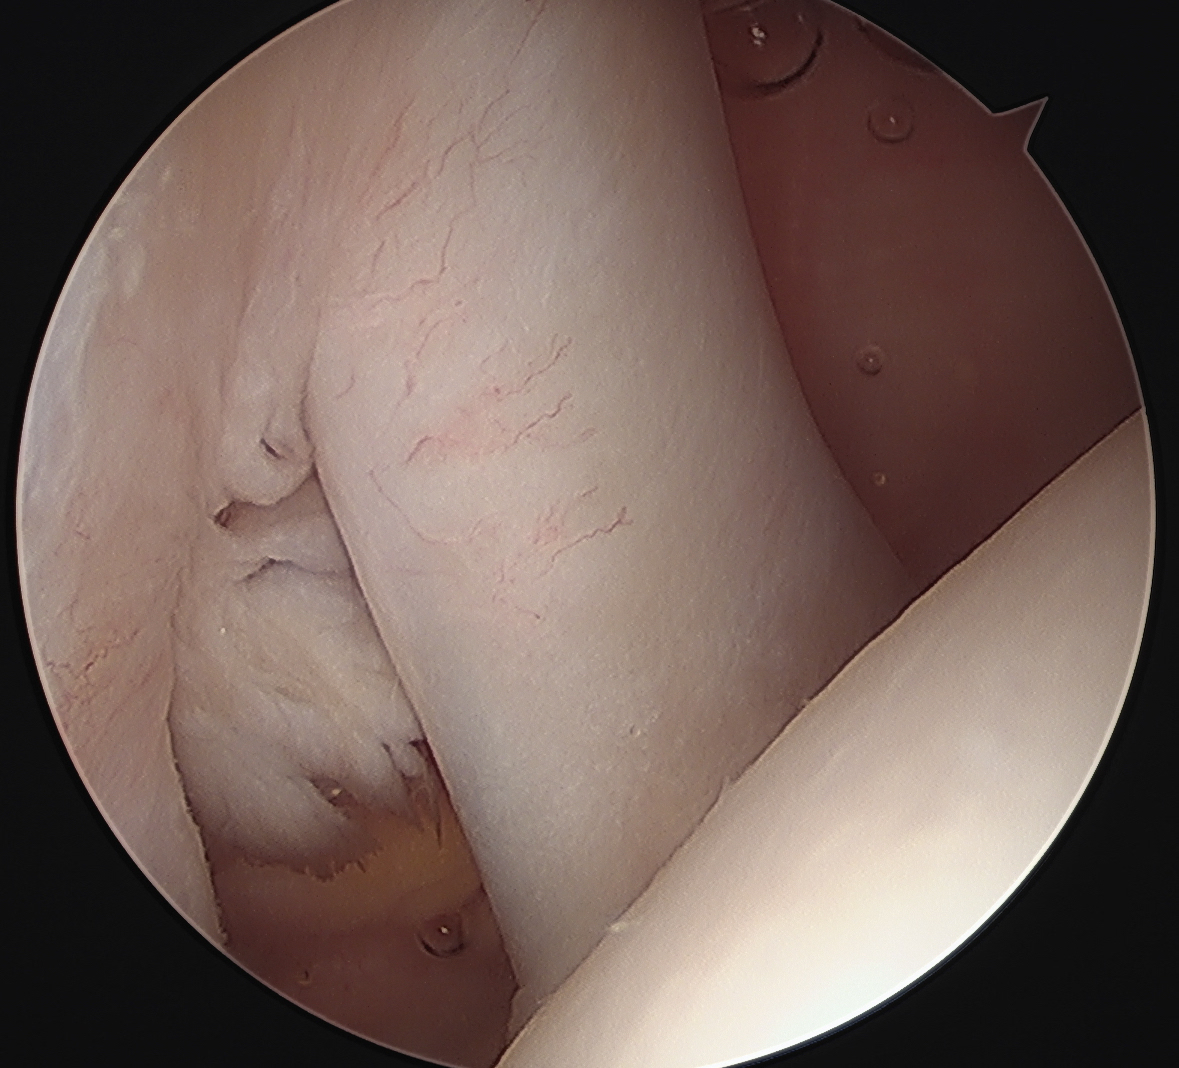

Arthroscopy

Medial subluxation of LHB

Medial subluxation of LBH with subscapularis tear